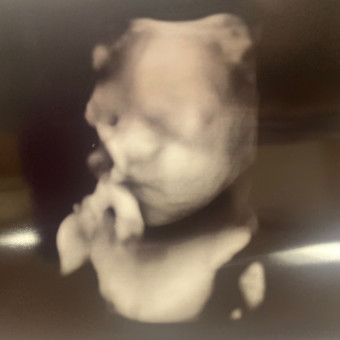

Ms Brown's Baby Registry

Welcome DeMarius